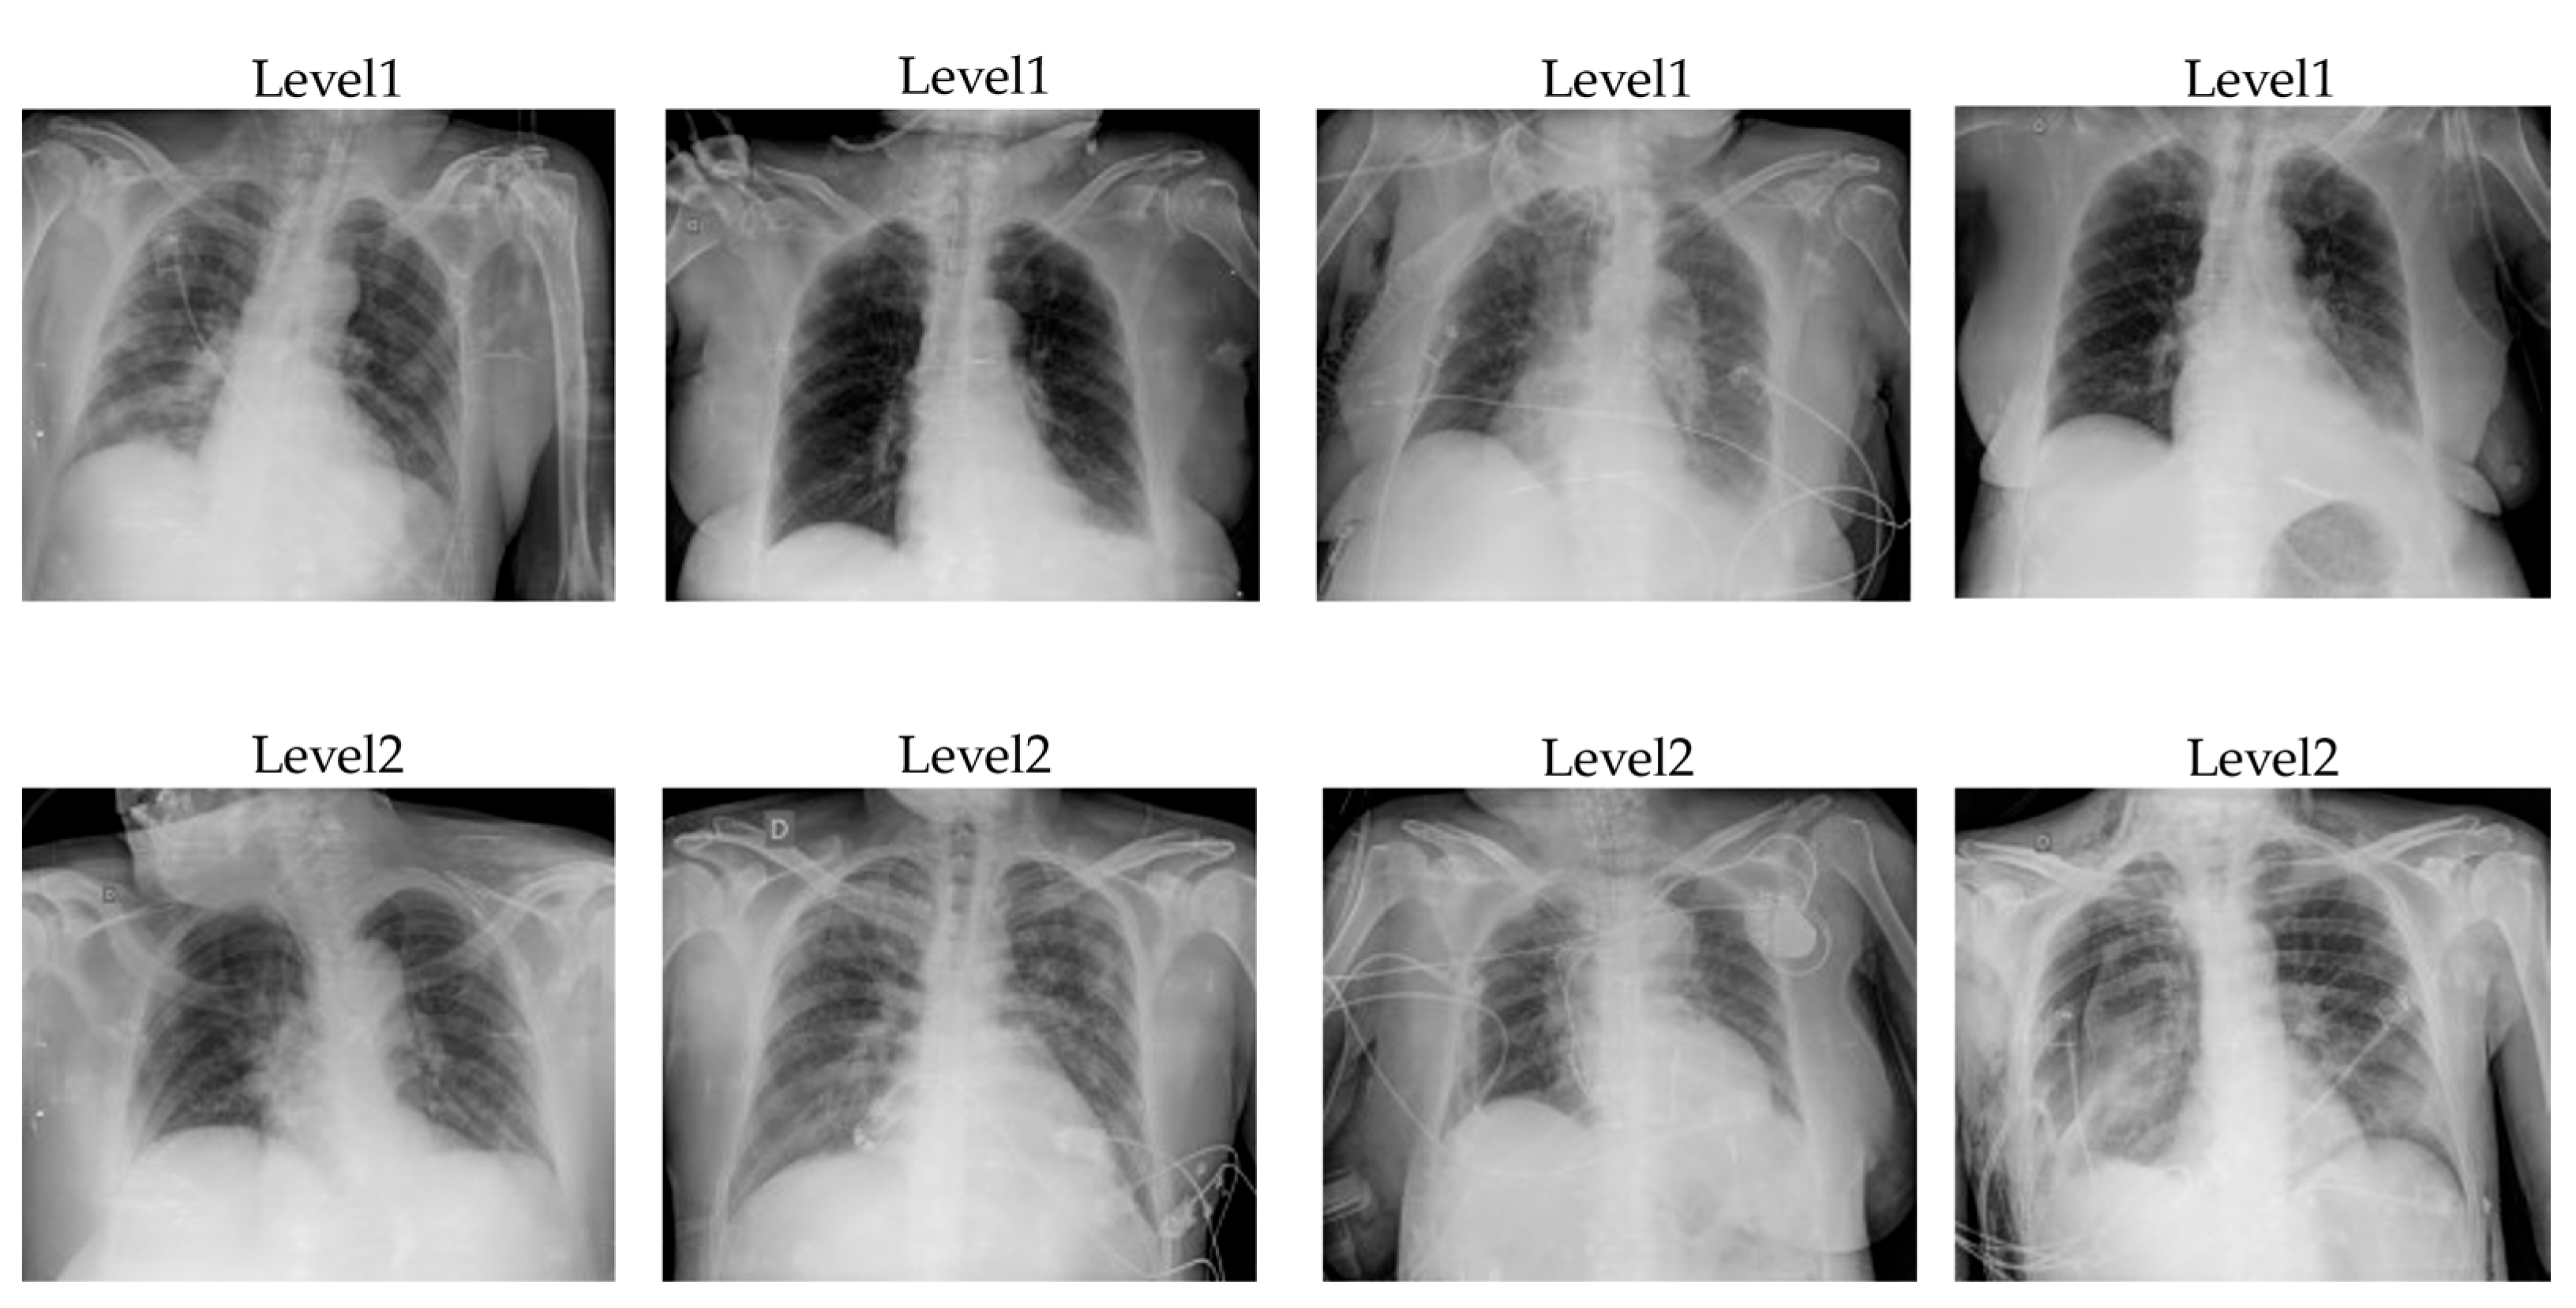

2.2.5. Hybrid EfficientNet and DOLG

The Hybrid EfficientNet and DOLG [55] won the Google Landmark Competition 2021 with the highest recognition performance on the over 200,000 classes. The author implemented the model by enhancing the original DOLG [56] with some adjustments to improve the recognition capability. At first, the author used the EfficientNet [57] which was pre-trained on the ImageNet dataset as an encoder. Then the author added a local branch after the third EfficientNet block and extracted those 1024 dimensions of local features by using three dilated convolutions where parameters were different per each model. The output of the fourth EfficientNet was projected to 1024 dimensions and those fused features accumulate using the average pooling before they were fed into the fully connected layers. The model used the subcenter arc face as the loss function contains dynamic margins for predicting thousands of classes. Overview architecture of Hybrid EfficientNet and DOLG illustrates in Figure 3 with EfficientNet-B5 as a feature extractor and DOLG as a classifier.

Figure 3. Hybrid EfficientNet-B5 and DOLG architecture.